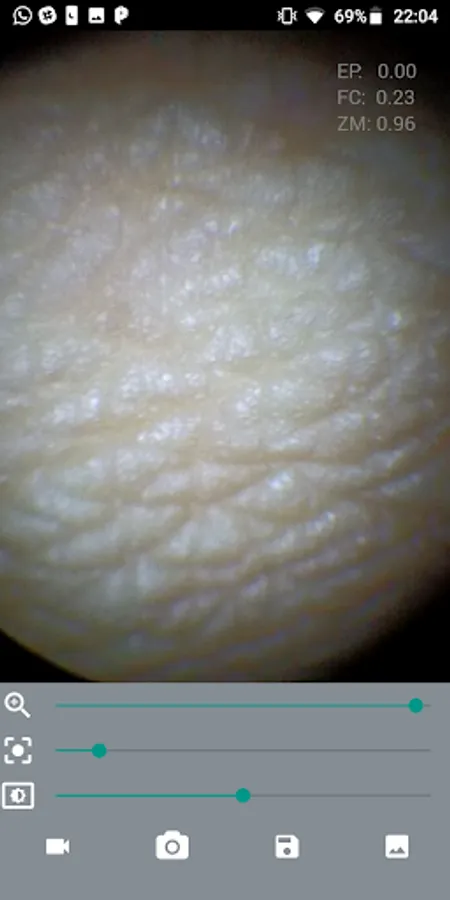

The M-Scope Mobile Endoscope is an application to be used in conjunction with the M-Scope kit, an endoscope coupling adapter + portable led light source, which can be used to attach a smartphone to an endoscope, to aid capture and sharing gallery of exams:

Nasofibrolaryngoscopy

Otoscopy

Hysteroscopy

Arthroscopy

Bronchoscopy

And other video-endoscopy exams and procedures in general.